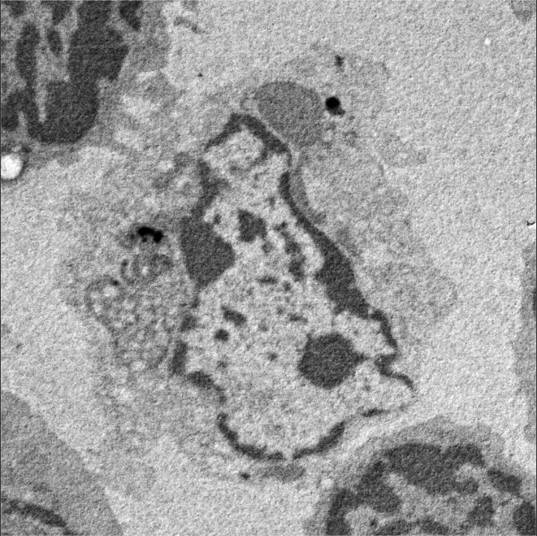

该研究通讯作者、信达生物制药集团新药生物与转化医学副总裁徐伟博士介绍,他和研究团队发现PD-L1抗体能够结合树突状细胞上的PD-L1,阻断PD-L1和B7.1的顺势结合和包埋,使得B7.1被释放出来,能够再次结合到T细胞上的CD28,遂形成超强的免疫突触,从而诱导T细胞抗肿瘤的活性。更重要的是,树突状细胞的作用也在两个关键临床试验里(肾癌和非小细胞肺癌)被证实,高表达树突状细胞的病人疗效显著增高。

自2014年首个PD-1药物上市以来,PD-1/PD-L1通路抑制剂已给临床抗肿瘤治疗带来了革命性突破。新研究使人认识到,PD-L1抗体能够直接激活树突状细胞获得抗肿瘤免疫功能。